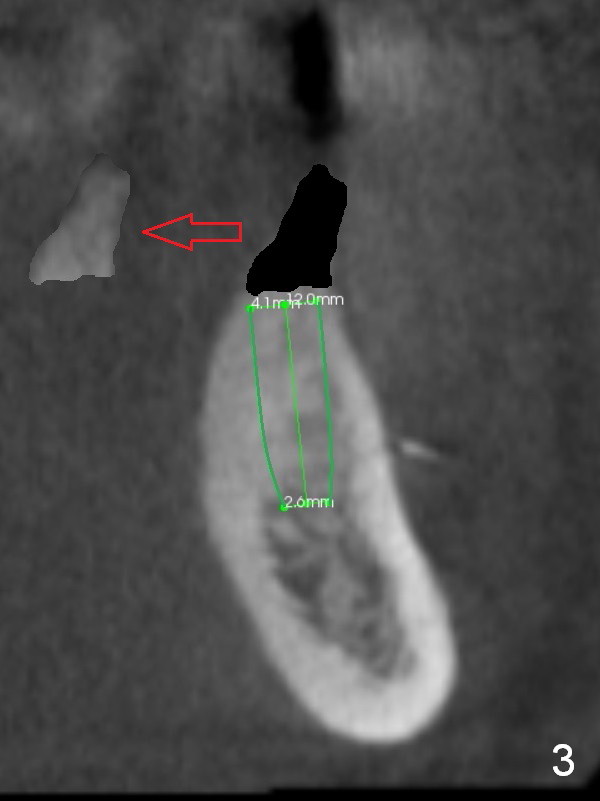

A 39-year-old man is pleased with implant placement at the lower right premolars (Fig.1: #28,29). He wants to have the same treatment at the lower left (#20,21), although the neighboring teeth need more urgent treatment. CBCT coronal sections at #21 (Fig.2) and 20 (Fig.4) show that the crest at the 1st premolar is particularly narrow and pointed. Since the Mental Foramen is at the 2nd premolar (arrowhead in Fig.4, 6 (sagittal section)), it seems appropriate to resect the atrophic crest by 6-7 mm at #21 (Fig.3 black area) and place a narrow implant low. It may invade the Incisive Nerve (Fig.7 brown cicle), which should be insignificant. A long abutment is expected at #21. A regular implant and abutment are expected at the 2nd premolar, similar to the right side. Smaller implants may be more appropriate (3.8 mm) to reduce postop bone resorption. In fact, the patient cracks the tooth #31. It seems to be nonsalvageable. In fact, what is to be done?